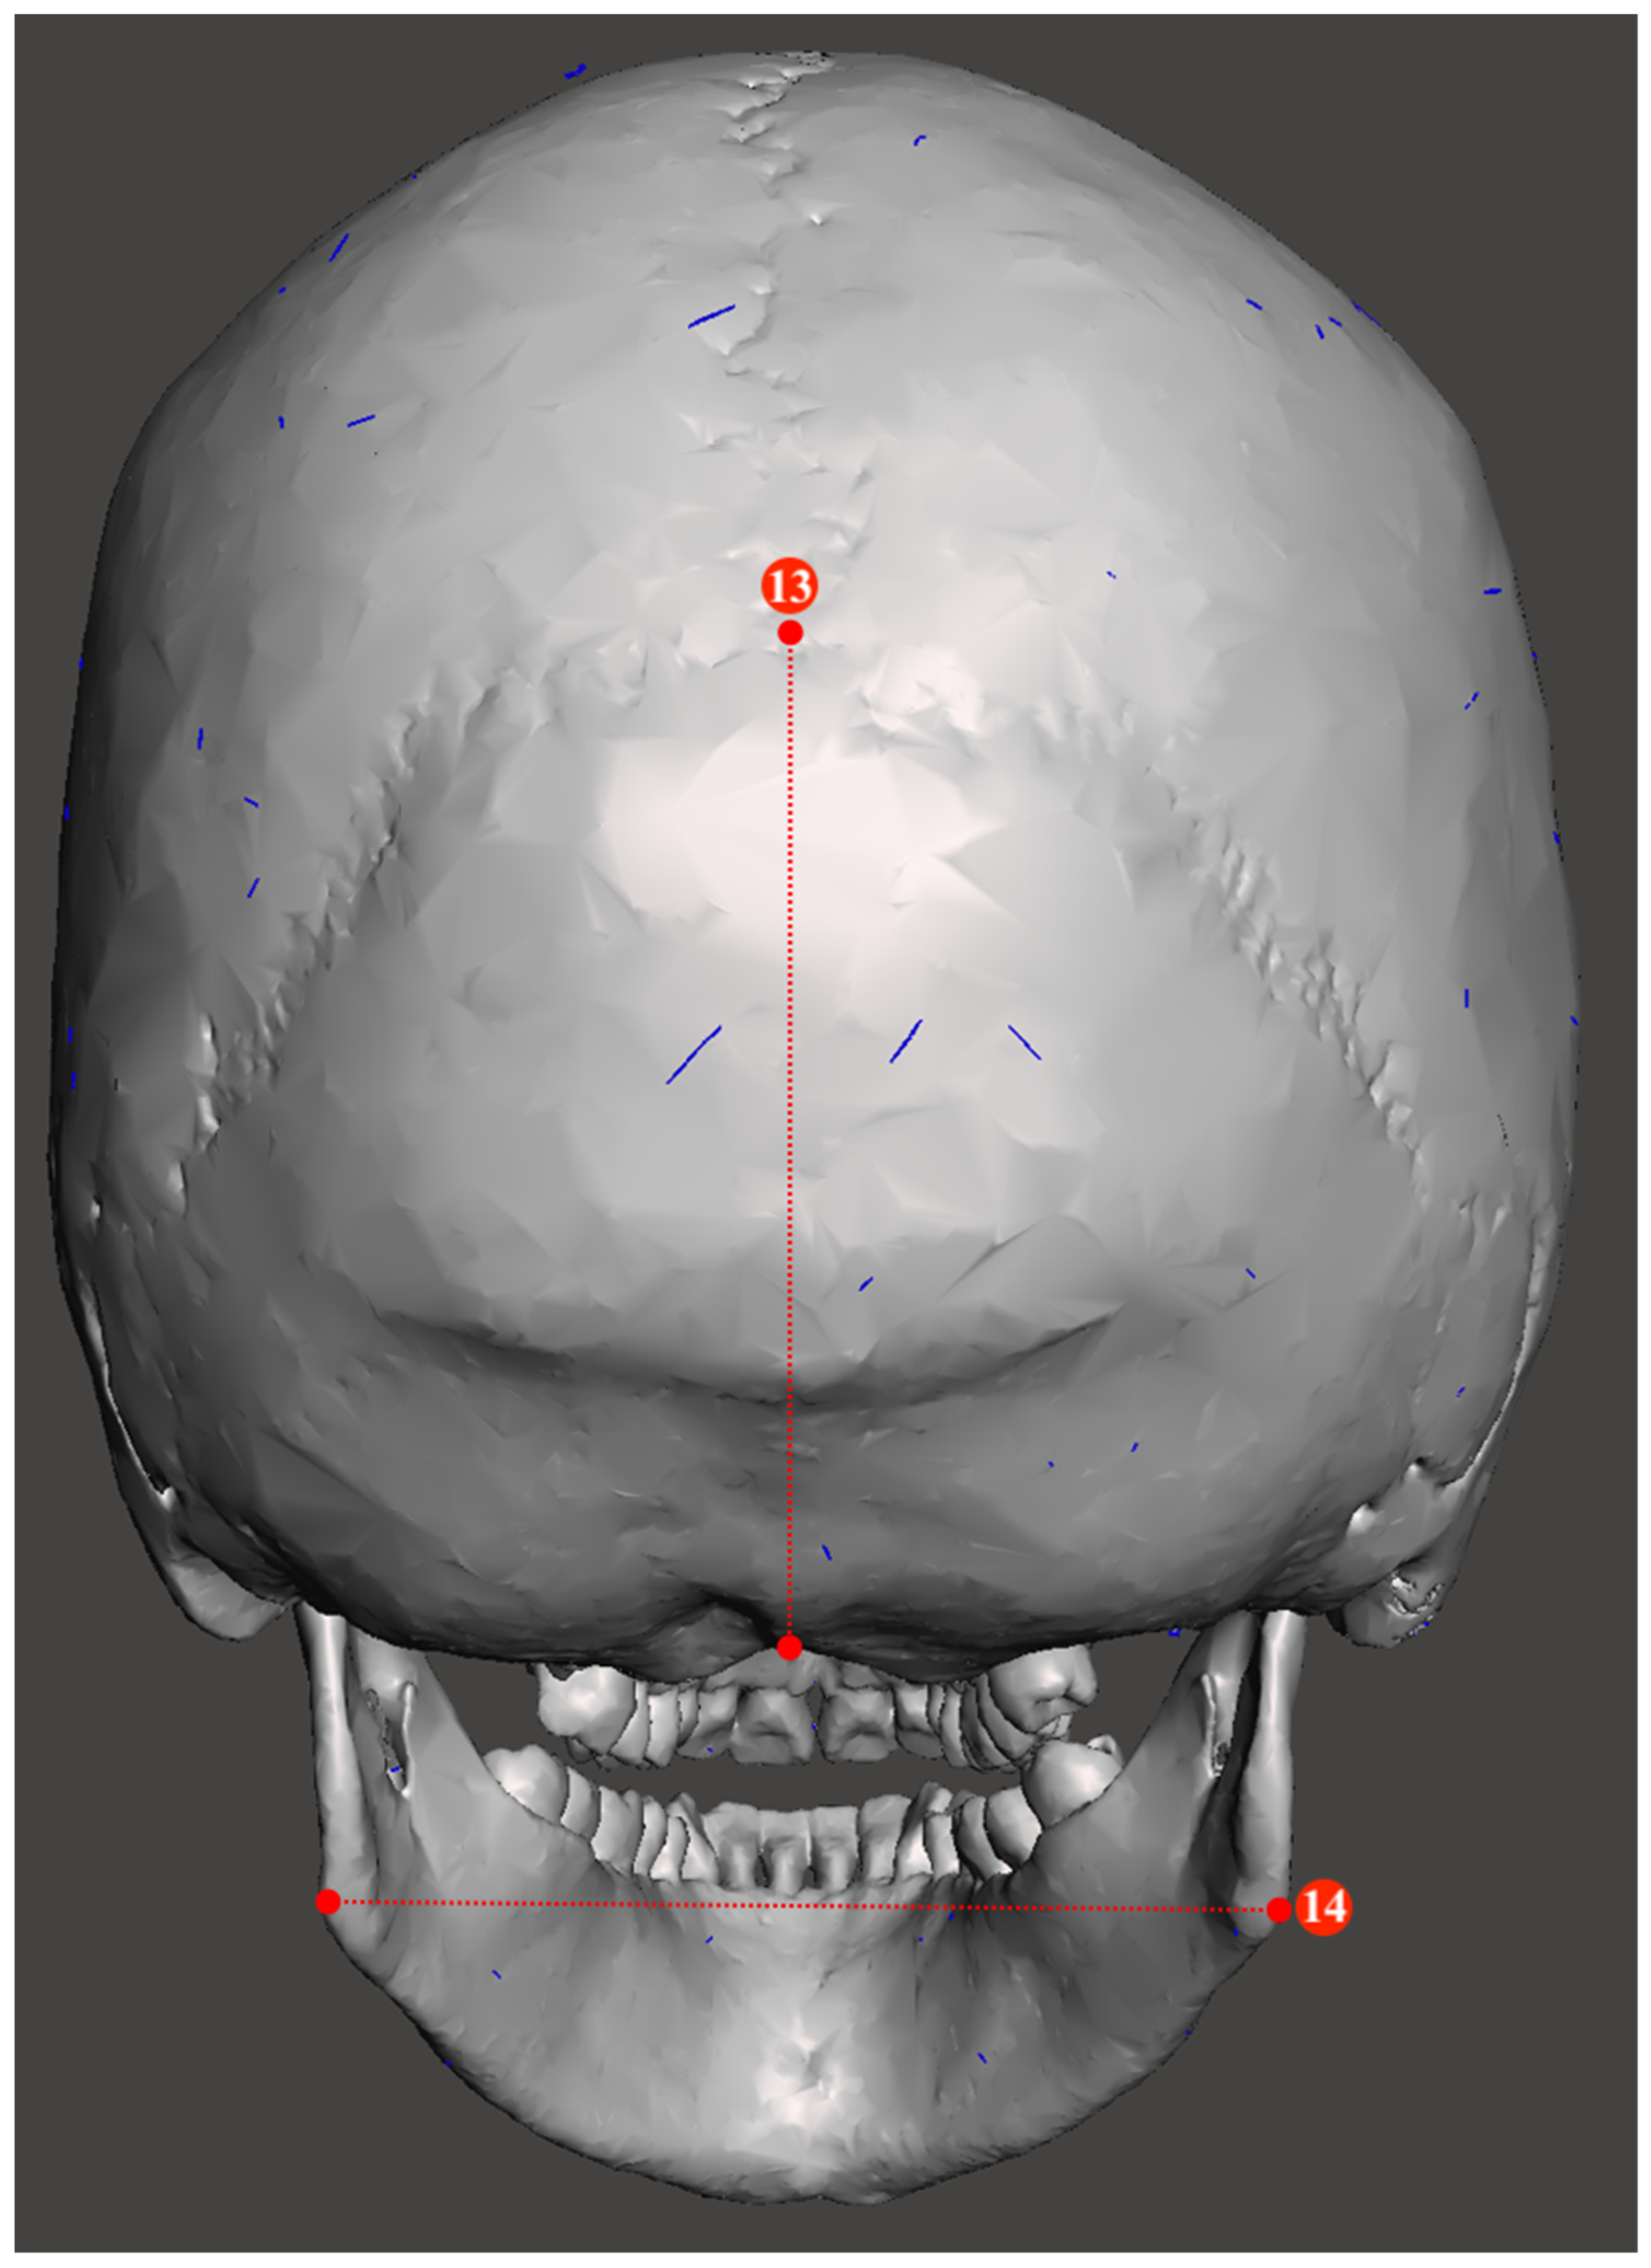

2.2. Study Sample Preparation and Data Collection

| Metric Measurements | |

|---|---|

| 1. Minimum frontal breadth (ft-ft) | 10. Bicondylar breadth (cdl-cdl) |

| 2. Orbital height | 11. Biauricular breadth (au-au) |

| 3. Upper facial height (n-pr) | 12. Foramen magnum breadth |

| 4. Parietal chord (b-l) | 13. Occipital chord (l-o) |

| 5. Glabella occipital length (g-op) | 14. Bigonial breadth (go-go) |

| 6. Mastoid length | 15. Basion–bregma height (ba-b) |

| 7. Mandibular length | 16. Basion–nasion length (ba-n) |

| 8. Maximum ramus height | 17. Frontal chord (n-b) |

| 9. Bizygomatic breadth (zy-zy) | 18. Nasal height (n-ns) |